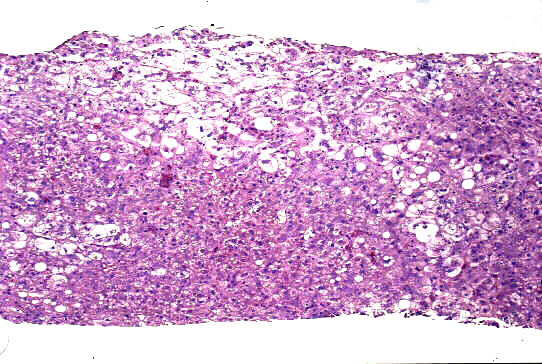

標本;HE,Azan,HBsAgオルセイン&鍍銀の4染色

- 小葉構造;P-P bridging hepatic necrosisをみるも保持されている

- 門脈域;中等度までの線維性拡大、中等度までの単核球主体の炎症性細胞浸潤、小葉間胆管の障害像、細胆管増生、胆汁栓

- 実質域;架橋形成性壊死 (bridging hepatic necrosis)、肝細胞の風船様膨化と再生性肝細胞、小ないし中滴性脂肪沈着を部分的にみる、羽毛状変性と風船様膨化、合胞性多核巨細胞の出現、ロゼット形成(偽腺管構造)、胞体内凝集傾向、核内空胞

肝細胞にビリルビン色素、Ground-glass所見は認めない

病理組織診断;急性肝炎、架橋形成性壊死を伴う(重症型)

Acute hepatitis with bridging necrosis